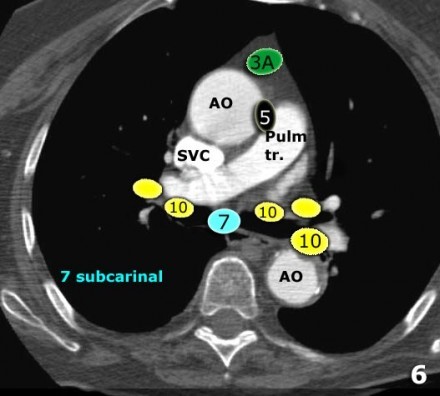

8. Linfonodos Paraesofageanos

Estes linfonodos estão abaixo dos linfonodos carinais e se estendem caudalmente até o diafragma.

9. Linfonodos do ligamento Pulmonar

Linfonodos do ligamento pulmonar estão dentro do ligamento pulmonar, incluindo aqueles na parede posterior e inferior da veia pulmonar inferior.

O ligamento pulmonar é a extensão inferior das reflexões da pleura mediastinal que cercam o hilos.